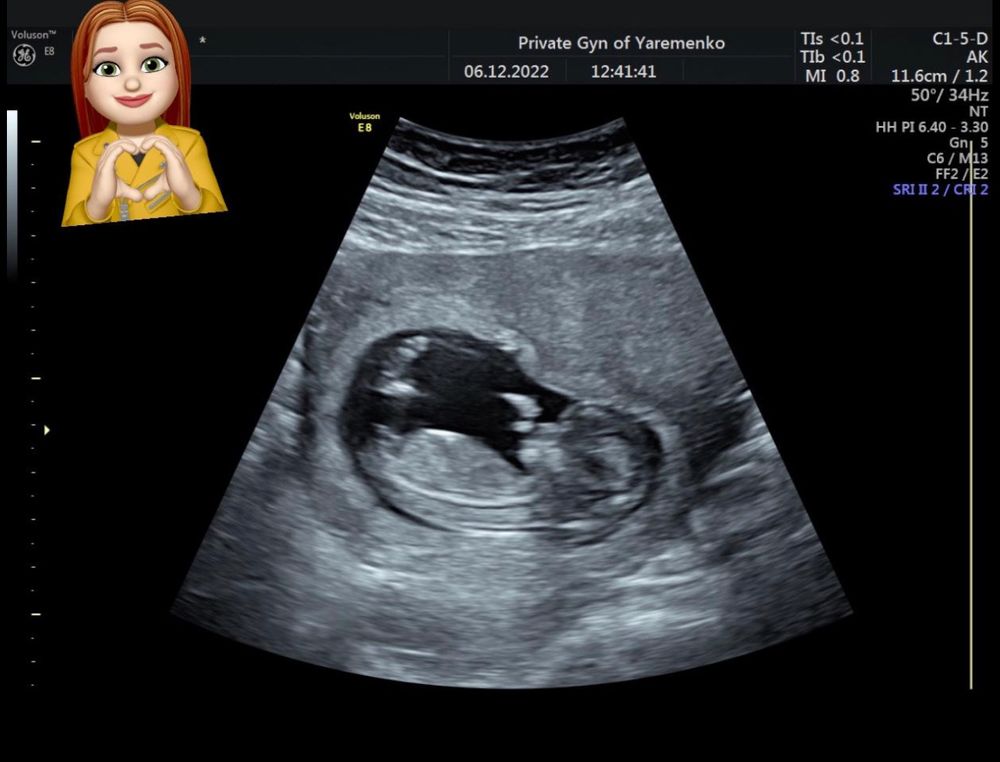

Первый скрининг 🥰

По узи всё хорошо, кроха растет и показала нам такие танцы 😍

Врач записал нам это всё на видео и сделал фото 🥰

Предположительно у нас девочка 👧

Ну если верить отзывам, то врач этот лучший в городе и только подтверждает свои предположения на 19 недели ☺️

Яременко фамилия узиста, принимает на холодной горе

Candy cola, он мне начал показывать там бугорок, мол если бы это был парень, то смотрел бы этот бугорок вверх, а тут мол нет

А мне если честно не понятно где там бугорок и куда он смотрит 🫣😅

Анастасия, если вот эта полосочка (где должен быть писюн)))) параллельна линии спинки, то это девочка😄